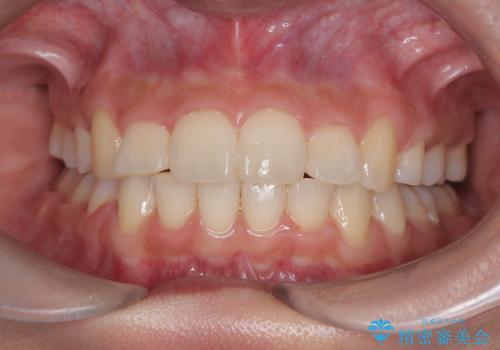

凸凹を綺麗にしたい。表側ワイヤー矯正

担当医 河口智英